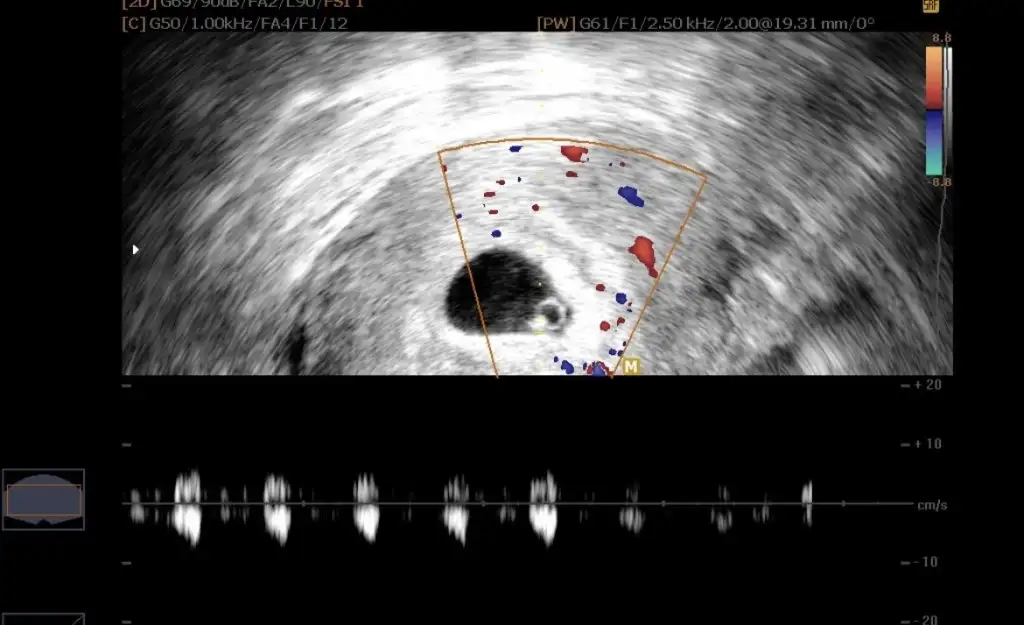

Bende bugun doktoruma gittim. 7 haftalik olmus yavrum🥹, resmini koyacagim cinsiyet hakkinda yorumu olan varsa sevinirim :)

CCCA609F-67BD-4208-819D-31F7483FB0C9.webp